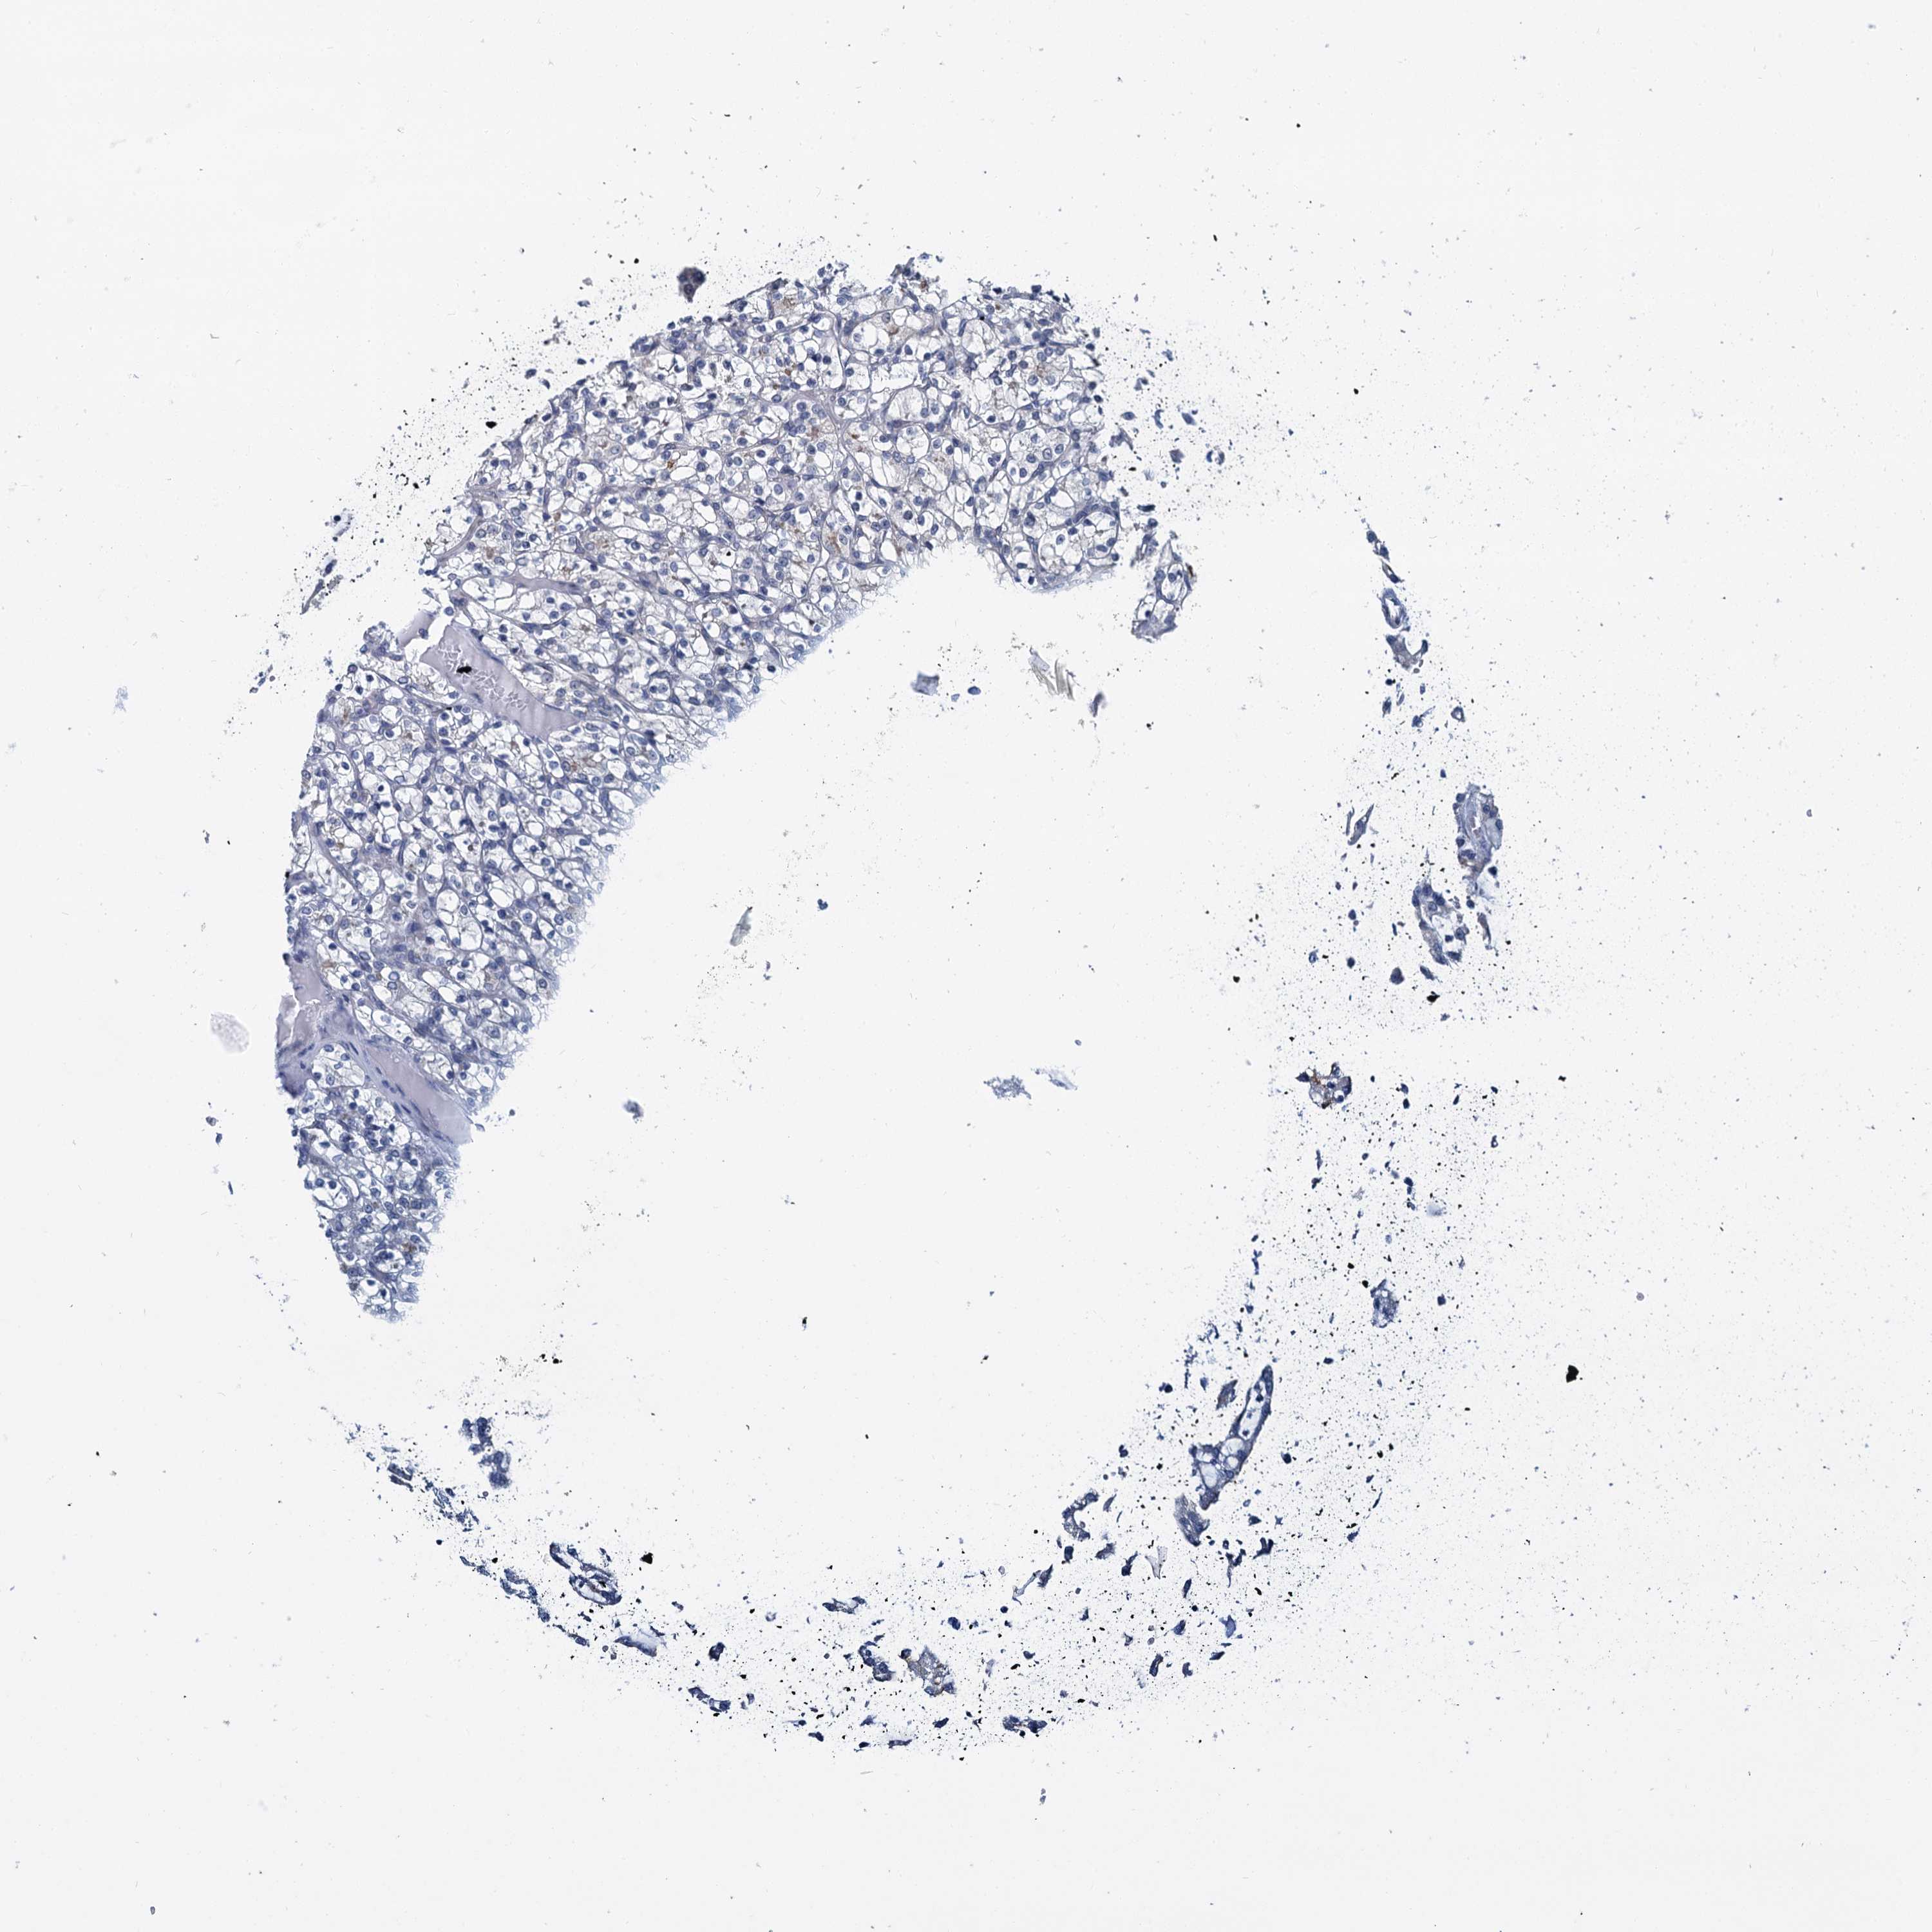

KIDNEY RENAL CLEAR CELL CARCINOMA (VALIDATION) - Interactive survival scatter ploti

The Survival Scatter plot shows the clinical status (i.e. dead or alive) for all individuals in the patient cohort, based on the same data that underlies the corresponding Kaplan-Meier plots. Patients that are alive at last time for follow-up are shown in blue and patients who have died during the study are shown in red.

The x-axis shows the expression levels (FPKM) of the investigated gene in the tumor tissue at the time of diagnosis. The y-axis shows the follow-up time after diagnosis (years). Both axes are complimented with kernel density curves demonstrating the data density over the axes. The top density plot shows the expression levels (FPKM) distribution among dead (red) and alive patients (blue). The right density plot shows the data density of the survived years of dead patients with high and low expression levels respectively, stratified using the cutoff indicated by the vertical dashed line through the Survival Scatter plot. This cutoff is automatically defined based on the FPKM cutoff that minimizes the p-score. The cutoff can be changed by dragging the vertical line or by entering a cutoff value in the square labeled "Current cut-off".

Under the Survival Scatter plot the p-score landscape (black curve; left axis) is shown together with dead median separation (red curve; right axis). Dead median separation is the difference in median mRNA expression between patients who have died with high and low expression, respectively. It is calculated as follows: median FPKM expression of dead patients with high expression - median FPKM expression of dead patients with low expression. This is intended to aid the user in visually exploring custom cutoffs and the associated p-scores and dead median separation.

Individual patient data is displayed and can be filtered by clicking on one or more of the category buttons on the top of the page. Categories describing expression level and patient information include: high, low, alive, dead, female, male and tumor stages. The scale of the x-axis can be toggled between linear and log-scale by clicking on the "x log" button. Mouse-over function shows TCGA ID, patient information and mRNA expression (FPKM) for each patient.

& Survival analysisi

Kaplan-Meier plots summarize results from analysis of correlation between mRNA expression level and patient survival. Patients were divided based on level of expression into one of the two groups "low" (under cut off) or "high" (over cut off). X-axis shows time for survival (years) and y-axis shows the probability of survival, where 1.0 corresponds to 100 percent.

MIOX is validated prognostic, high expression is favorable in Kidney Renal Clear Cell Carcinoma (validation)

: 12.54

Average pTPM 104.3

Number of samples 100